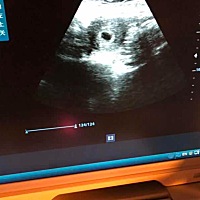

谁能看出来这个形状是男孩还是女孩。